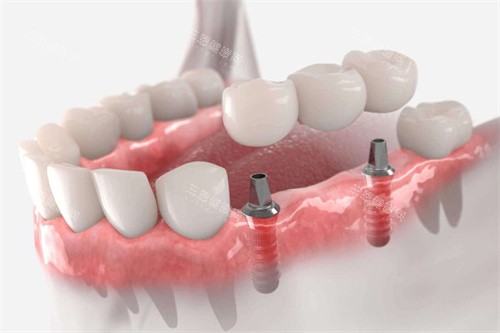

很多人以为全口种植牙就是“种满口牙”,其实现在主流用的是all-on-4/6技术,也就是用4-6颗种植体支撑全口牙冠,创伤小、费用也比种28颗牙便宜一半。

缺牙三颗种植连桥冠